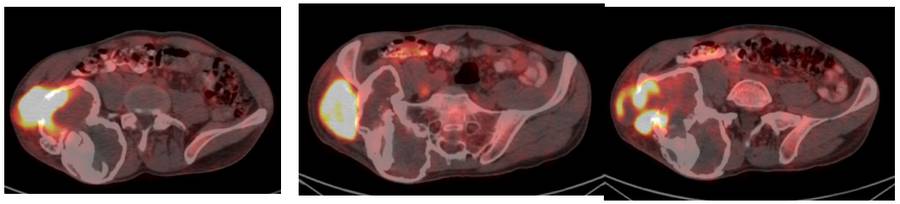

Ameliyat Öncesi: PET_CT’de sağ ilaik kanat dış kısımda artmış yoğun aktivite görülmekte